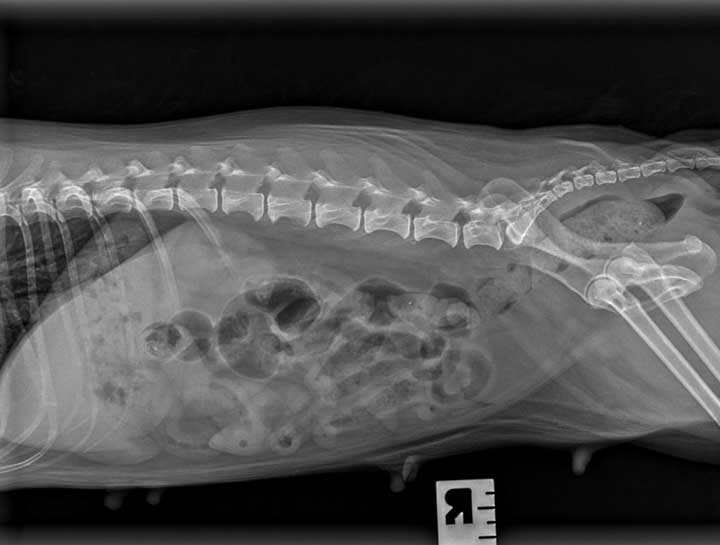

Pet Digital Radiology

Digital x-rays assist in diagnosing illness & injury.